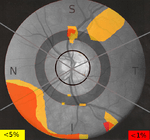

Presents RNFL thickness in colour with thick regions in red and yellow and thin regions in blue and green.

For healthy eye, the image will show yellow and red colour in superior and inferior at NFL regions. But, in glaucoma, the image is absence of red and yellow colours. Superiorly and inferiorly more uniform blue appearance. Picture indicates that the eye is at the advance stage of the disease.

Deviation map

The deviation map reveals the location and magnitude of RNFL thinning relative to a normal value. This normal value was generated as an average of people from various cultures. Defects are colour-coded based on probability of normality (e.g. yellow means that the probability is below 5% of that RNFL at that location is normal). A healthy eye has a clear deviation map.